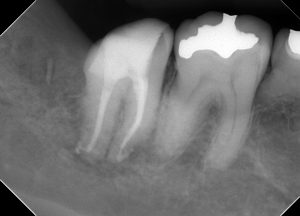

(治療後のレントゲン)

問題は無いと思われる。

この治療のポイントは、遠心側のう蝕の処置である。

拡大視野で虫歯を取り切り、電気メスで歯肉を切除&止血し、隔壁用のCRを確実に接着させなければならない。

ここさえ終われば、あとは通法に従い、根管治療を行うだけだ。

半年間経過観察をし、問題ないため、補綴処置へ移行した。

(半年経過後のレントゲン)